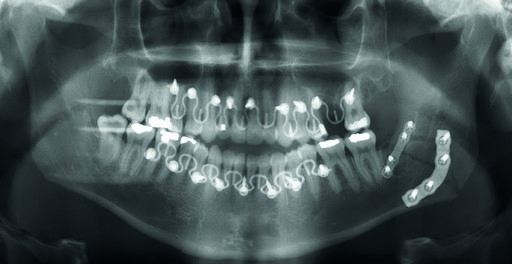

A 28 year old white male was subject to personal assault, and sustained a left mandibular angle fracture (Fig 1). The fracture was prestabilized with the Matrix Wave system and then fixated with a 4-hole miniplate 2.0 on the superior border and a 4-hole angulated universal fracture plate 2.4 along the inferior border. A pre-existing anterior open bite was noted and confirmed with the patient prior to presentation to the operating arena.

The MatrixWAVE plate was attached to the maxilla with screw placement in the inter-root spaces (Fig 2). A second MatrixWAVE plate was attached in corresponding position to the mandible, with screw placement in the inter-root spaces (Fig 3). Wires were placed around the plate hooks to bring the dental arches into occlusion. Note the preexisting anterior open bite (Fig 4). Careful adjustment of the MatrixWAVE plate and wiring in the region of the mandibular fracture allowed the bone fragments to be precisely aligned without the requirement for screw repositioning (Fig 5). The postoperative panoramic x-ray (Fig 6) shows the two MatrixWAVE plates in situ, with other plates used to fixate the left mandibular angle fracture. Note that a portion of the Matrix- WAVE plate was removed from the left molar region in the mandible (Fig 6).